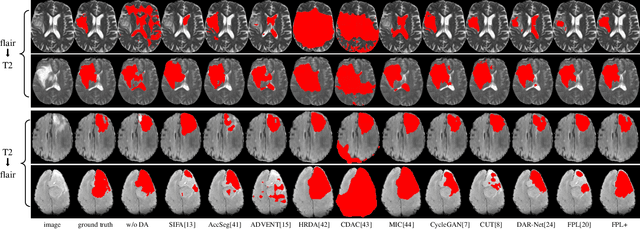

Abstract:Adapting a medical image segmentation model to a new domain is important for improving its cross-domain transferability, and due to the expensive annotation process, Unsupervised Domain Adaptation (UDA) is appealing where only unlabeled images are needed for the adaptation. Existing UDA methods are mainly based on image or feature alignment with adversarial training for regularization, and they are limited by insufficient supervision in the target domain. In this paper, we propose an enhanced Filtered Pseudo Label (FPL+)-based UDA method for 3D medical image segmentation. It first uses cross-domain data augmentation to translate labeled images in the source domain to a dual-domain training set consisting of a pseudo source-domain set and a pseudo target-domain set. To leverage the dual-domain augmented images to train a pseudo label generator, domain-specific batch normalization layers are used to deal with the domain shift while learning the domain-invariant structure features, generating high-quality pseudo labels for target-domain images. We then combine labeled source-domain images and target-domain images with pseudo labels to train a final segmentor, where image-level weighting based on uncertainty estimation and pixel-level weighting based on dual-domain consensus are proposed to mitigate the adverse effect of noisy pseudo labels. Experiments on three public multi-modal datasets for Vestibular Schwannoma, brain tumor and whole heart segmentation show that our method surpassed ten state-of-the-art UDA methods, and it even achieved better results than fully supervised learning in the target domain in some cases.